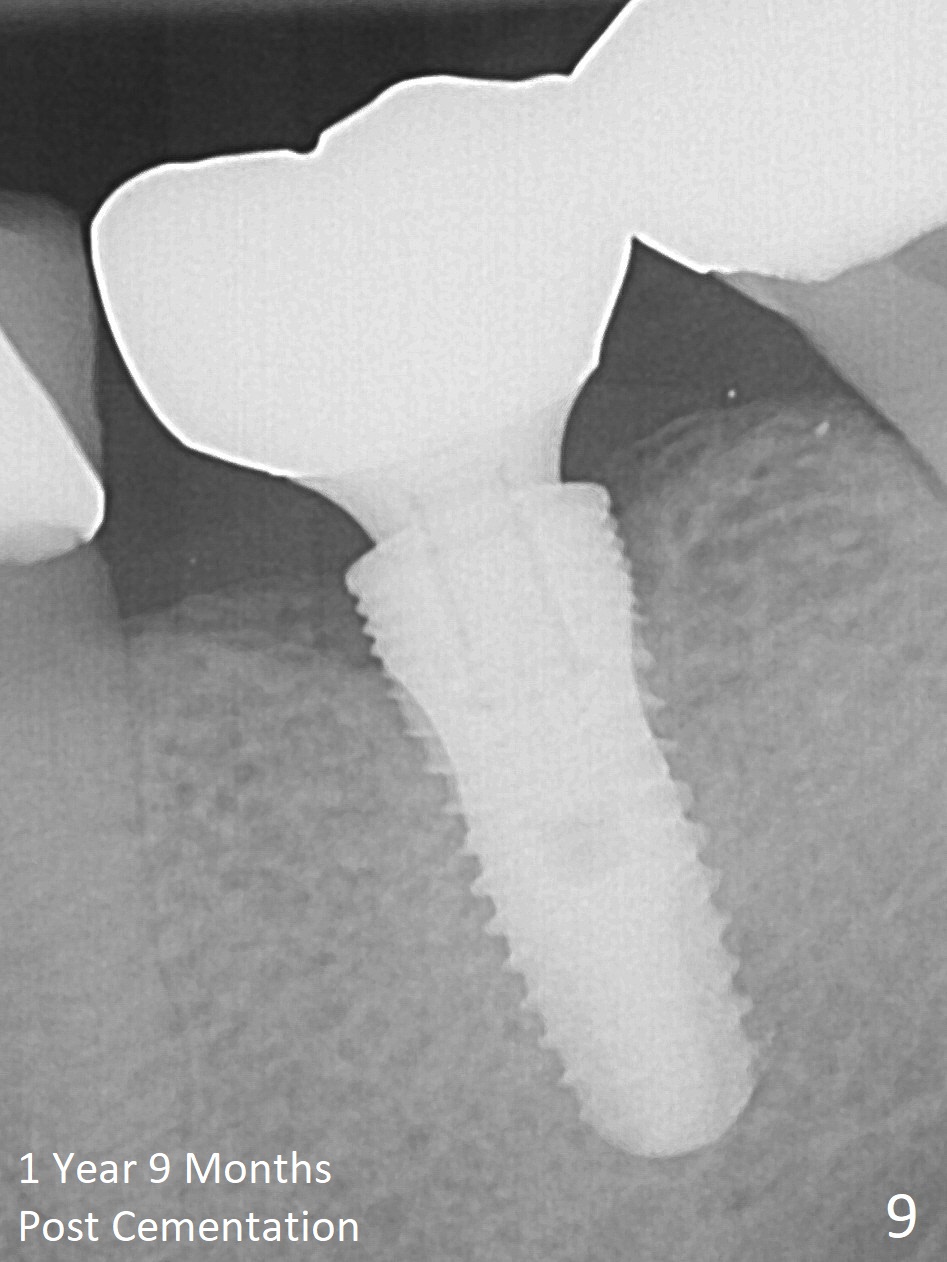

Two months post impression (4 months postop), the patient returns for cementation. The provisional is perforated again in the occlusal surface (Fig.7 P). When the provisional is removed, a shallow trough forms around the abutment (Fig.8*). The bony defect appears to be repaired 1 year 9 months post cementation (Fig.9).